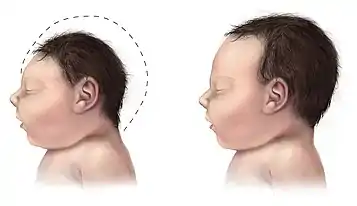

The main signs of achalasia microcephaly syndrome involve the manifestation of each individual disease associated with the condition. Microcephaly can be primary, where the brain fails to develop properly during pregnancy, or secondary, where the brain is normal sized at birth but fails to grow as the child ages.[2] Abnormalities will be observed progressively after birth whereby the child will display stunted growth and physical and cognitive development. The occipital-frontal circumference will be at or near the extreme lower end, the third percentile, indicating microcephaly.[3] There are both genetic and behavioural causes of microcephaly.[2]

Alongside prominent dysphagia, the child will have microcephaly, which is characterised by an abnormally small head. Mild scaphocephaly may also be observed.[3] This can manifest upon or after birth.[2] Slow cognitive and fine motor development as well as delayed speech will be observed.[3][6] Craniofacial dysmorphism, such as a globular-shaped nose, micrognathia and a flattened forehead may also be involved, but is not observed in all cases.[9][6] Camptodactyly of some fingers can also manifest.[10]

Microcephaly can manifest due to a variety of reasons, these include: TORCH infections, chromosomal and biochemical abnormalities and can be transmitted as an autosomal recessive, dominant or X-linked disorder.[12] It is most commonly caused by congenital infections due to viruses such as cytomegalovirus, herpes simplex virus and Zika virus.[15] The severe reduction of neural progenitors and neurones as a result of cell cycle arrest and neural progenitor death due to viral infection leads to microcephaly.[15] There are two types of microcephaly, primary, occurring before thirty-two weeks of gestation or secondary, after birth.[2] A reduced production of neurones is attributed to primary microcephaly whilst decreased dendritic connection is thought to cause secondary microcephaly, all amounting to an estimated brain size that is significantly smaller than average.[2] Further, the cerebral cortex occupies 55% of the human brain, therefore, most microcephalic people are mentally retarded.[2][4] Developmental delay in motor and communication skills will result.[4] Congenital microcephaly has also been attributed to serine deficiencies that cause defects in two known enzymes: 3-phosphogycerate dehydrogenase and 3-phosphoserine phosphatase, leading to severe neurological abnormalities[16]

Microcephaly

Prenatal diagnosis of microcephaly is difficult due to the variability present in the causes of the disease.[8] Early detection, however, is important for consanguineous parents as an autosomal recessive inheritance is highly implicated for microcephaly.[12][8] Anomaly scans during pregnancy can be used to calculate the ratio between the head/abdominal circumference and head circumference/femur length which are used calculate and diagnose microcephaly.[8] Ultrasound scans have also led to the accidental discovery of microcephaly, however this occurrence is an anomaly.[8]

Prenatal diagnosis is further complicated when microcephaly manifests with achalasia as it is only possible to detect symptoms shortly after the first trimester and early into the second.[8] Consequently, microcephaly is usually diagnosed after the onset of achalasia by eighteen months or older.[10] An occipital-frontal head circumference of less than three standard deviations is an indication of microcephaly.[2] Radiography and NMR imaging of the skull can also be utilised.[9] A physical examination of height and weight proportions as well as IQ and motor development is implemented for further confirmation as not all children with microcephaly have abnormal development[3][15] A positive test will show normal to abnormal proportions, a low IQ and slow motor development.